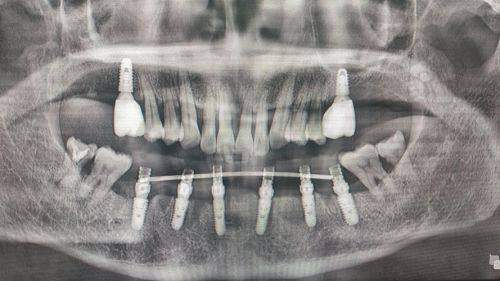

1. 数字化精细种植:采用3D导板导航技术,支持即拔即种、即刻修复,配备韩国奥齿泰、瑞士ITI等8个进口种植系统,满足不同骨条件患者需求。

医院的数字化导板种植牙技术代表嘉兴地区种植领域较高等水平:通过CBCT扫描获取牙槽骨三维数据,计算机自动生成手术导板,精细控制种植体植入的角度、深度和扭矩。与传统种植相比,该技术将手术时间缩短40%,出血量减少70%,神经损伤风险降低至0.3%。针对骨量不足患者,创新采用"即刻种植+GBR骨增量"联合术式,成功几率达96.7%,解决了传统种植需要3 - 6个月骨愈合等待期的问题。

梁桂植:韩国庆熙大学口腔医学博士,医院特聘种植技术总监,每月定期坐诊。擅长即刻负重种植、上颌窦内外提升等复杂手术,在韩国开展"All - on - 4一日重建"手术超500例,其改良式骨劈开技术使种植体存活率达98.9%。

5. 半口ALL - ON - 4种植:23800元起(含8颗种植体+桥架)